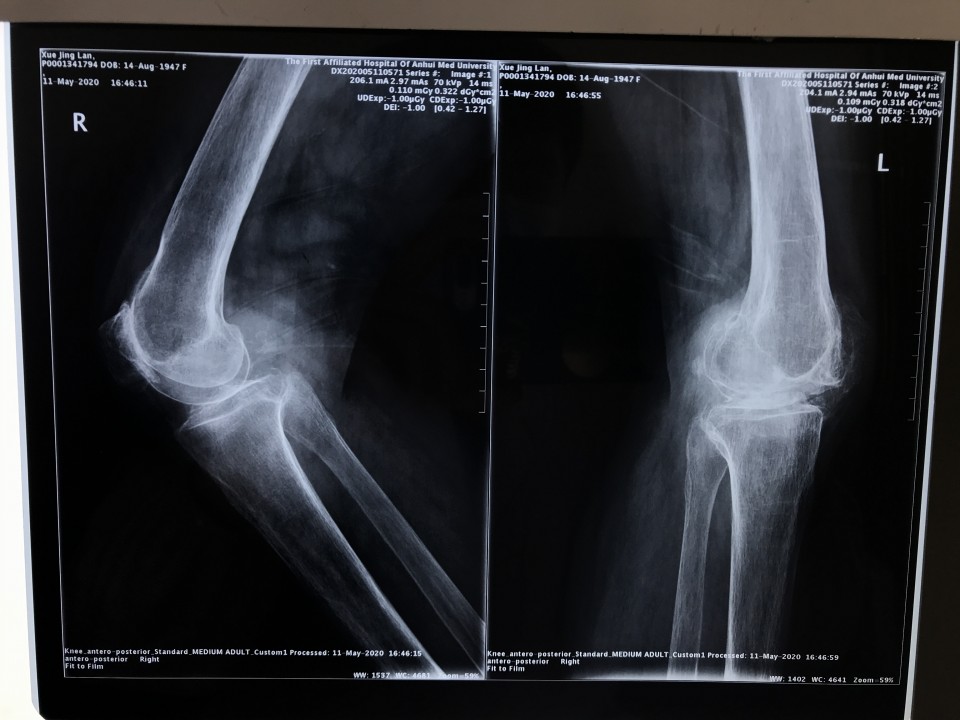

5月11日,一位72岁女性患者因“双膝关节疼痛伴活动受限8年,加重半年”入院,术前摄片提示双侧膝关节骨性关节炎。左侧膝关节伸直型僵直,屈伸活动度范围为0°。 我科胡孔足主任术前结合患者病史,体检及辅助检查,制定详实方案,先行左侧全膝关节置换术,术中采用TTO(胫骨结节截骨术),患者术后第二天下地正常行走,5月18日出院时已经能够完全自主抬腿,膝关节屈曲可达100°,减轻了患者的疼痛,明显提高了生活质量,疗效满意。